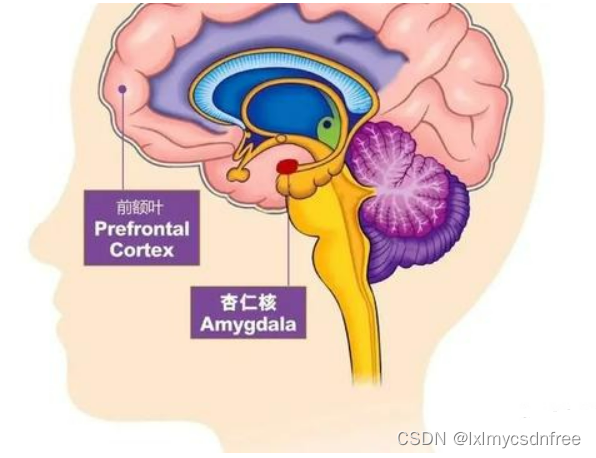

在情绪刺激过程中,其实前额叶也会参与情绪的管理,也会处理控制;杏仁体也会接受情绪方面的讯息,但是一旦杏仁体被完全激活(比如说PTSD记忆)那么杏仁体就会完全充血,完全进入自助模式,这个就是杏仁体劫持过程。人类在进化过程中已经把情绪基因植入到脑发育中了,比如恐惧、愤怒、害怕等;婴儿在出生时杏仁体中这些基本的情绪感知和处理的结构已经发育好了。

中立刺激通过与恐惧刺激配对,成为了条件刺激,在杏仁核留下了记忆痕迹。之后这种记忆通路的激活会产生自发性的恐惧反应。动物实验和对焦虑症患者的研究表明,前额叶抑制可以削弱恐惧表达,但不会将其擦除。随着压力恢复、环境改变或是时间流逝,原先的恐惧感会再度出现。

【脑结构的改变、认知变化】在焦虑的大脑中,杏仁核变得很大,回异常活跃;大脑中,除了杏仁核,还有额叶参与了焦虑的处理。杏仁核是情绪大脑的一部分。额叶就是认知大脑。只有当来自情绪大脑的信号压倒认知大脑并进入我们的意识时,我们才会感到焦虑。当杏仁核发出注意危险的警报时,前额叶皮层(PFC)应该像理性的顾问,启动分析处理信息,并帮你做出理性、合乎逻辑的反应。这个过程就像是踩刹车,抑制了被杏仁核夸大的信号。焦虑减弱了大脑部分联结,让理性反应受影响,焦虑会削弱杏仁核和前额叶皮层(PFC)之间的联系,这使杏仁核的刹车受损。焦虑也加强了大脑另一部分联结,使负面记忆留存,长期焦虑的大脑的海马体和杏仁核之间的连接性变得更强。其实当你焦虑时,压力会使大脑中处理长期和情境记忆的海马体收缩。海马体萎缩后,你的大脑保持记忆会有一定困难。然而麻烦的是,当你的海马体与杏仁核的联系比它与前额叶皮层的联系更紧密时,海马体就会保留与焦虑相关的记忆,可能记住的就是那些威胁、失败、危险,而不是存住快乐、成功和安.全的记忆。这会让你更加感到焦虑。